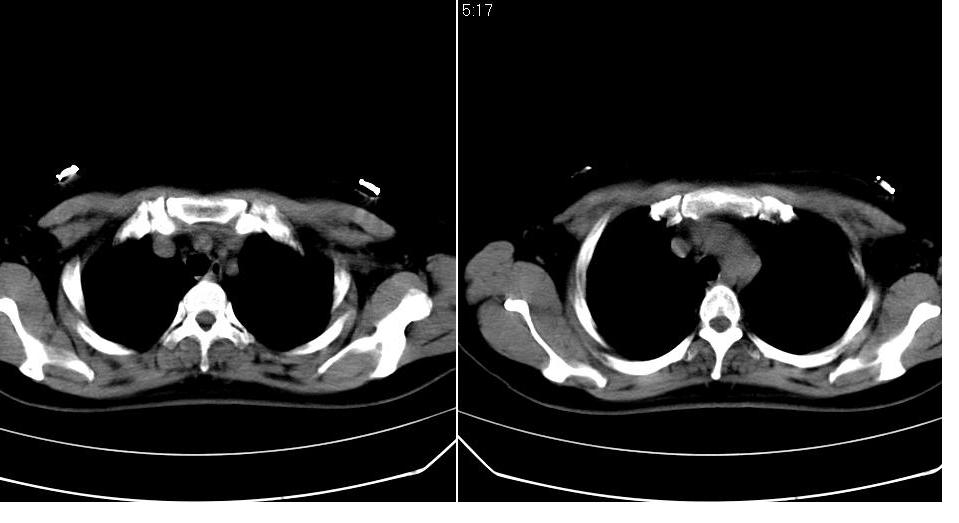

女 40岁,胸片体检发现右肺肿块,无任何症状。

下叶背段多发性小腺泡结节,考虑结核。

考虑右肺下叶背段继发性肺结核。